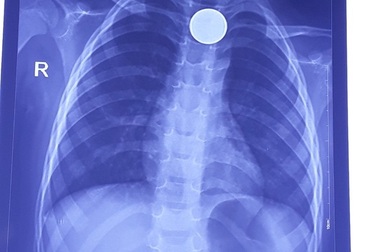

Sau tiếng khóc thét, đồng xu trôi tọt vào thực quản bé trai 3 tuổiTrên hình ảnh chụp X-quang, đồng xu tròn, sáng lóa nằm ngay ở 1/3 phần trên thực quản của bệnh nhi. Hóc dị vật đồng xu khiến em bé liên tục ọe, buồn nôn.